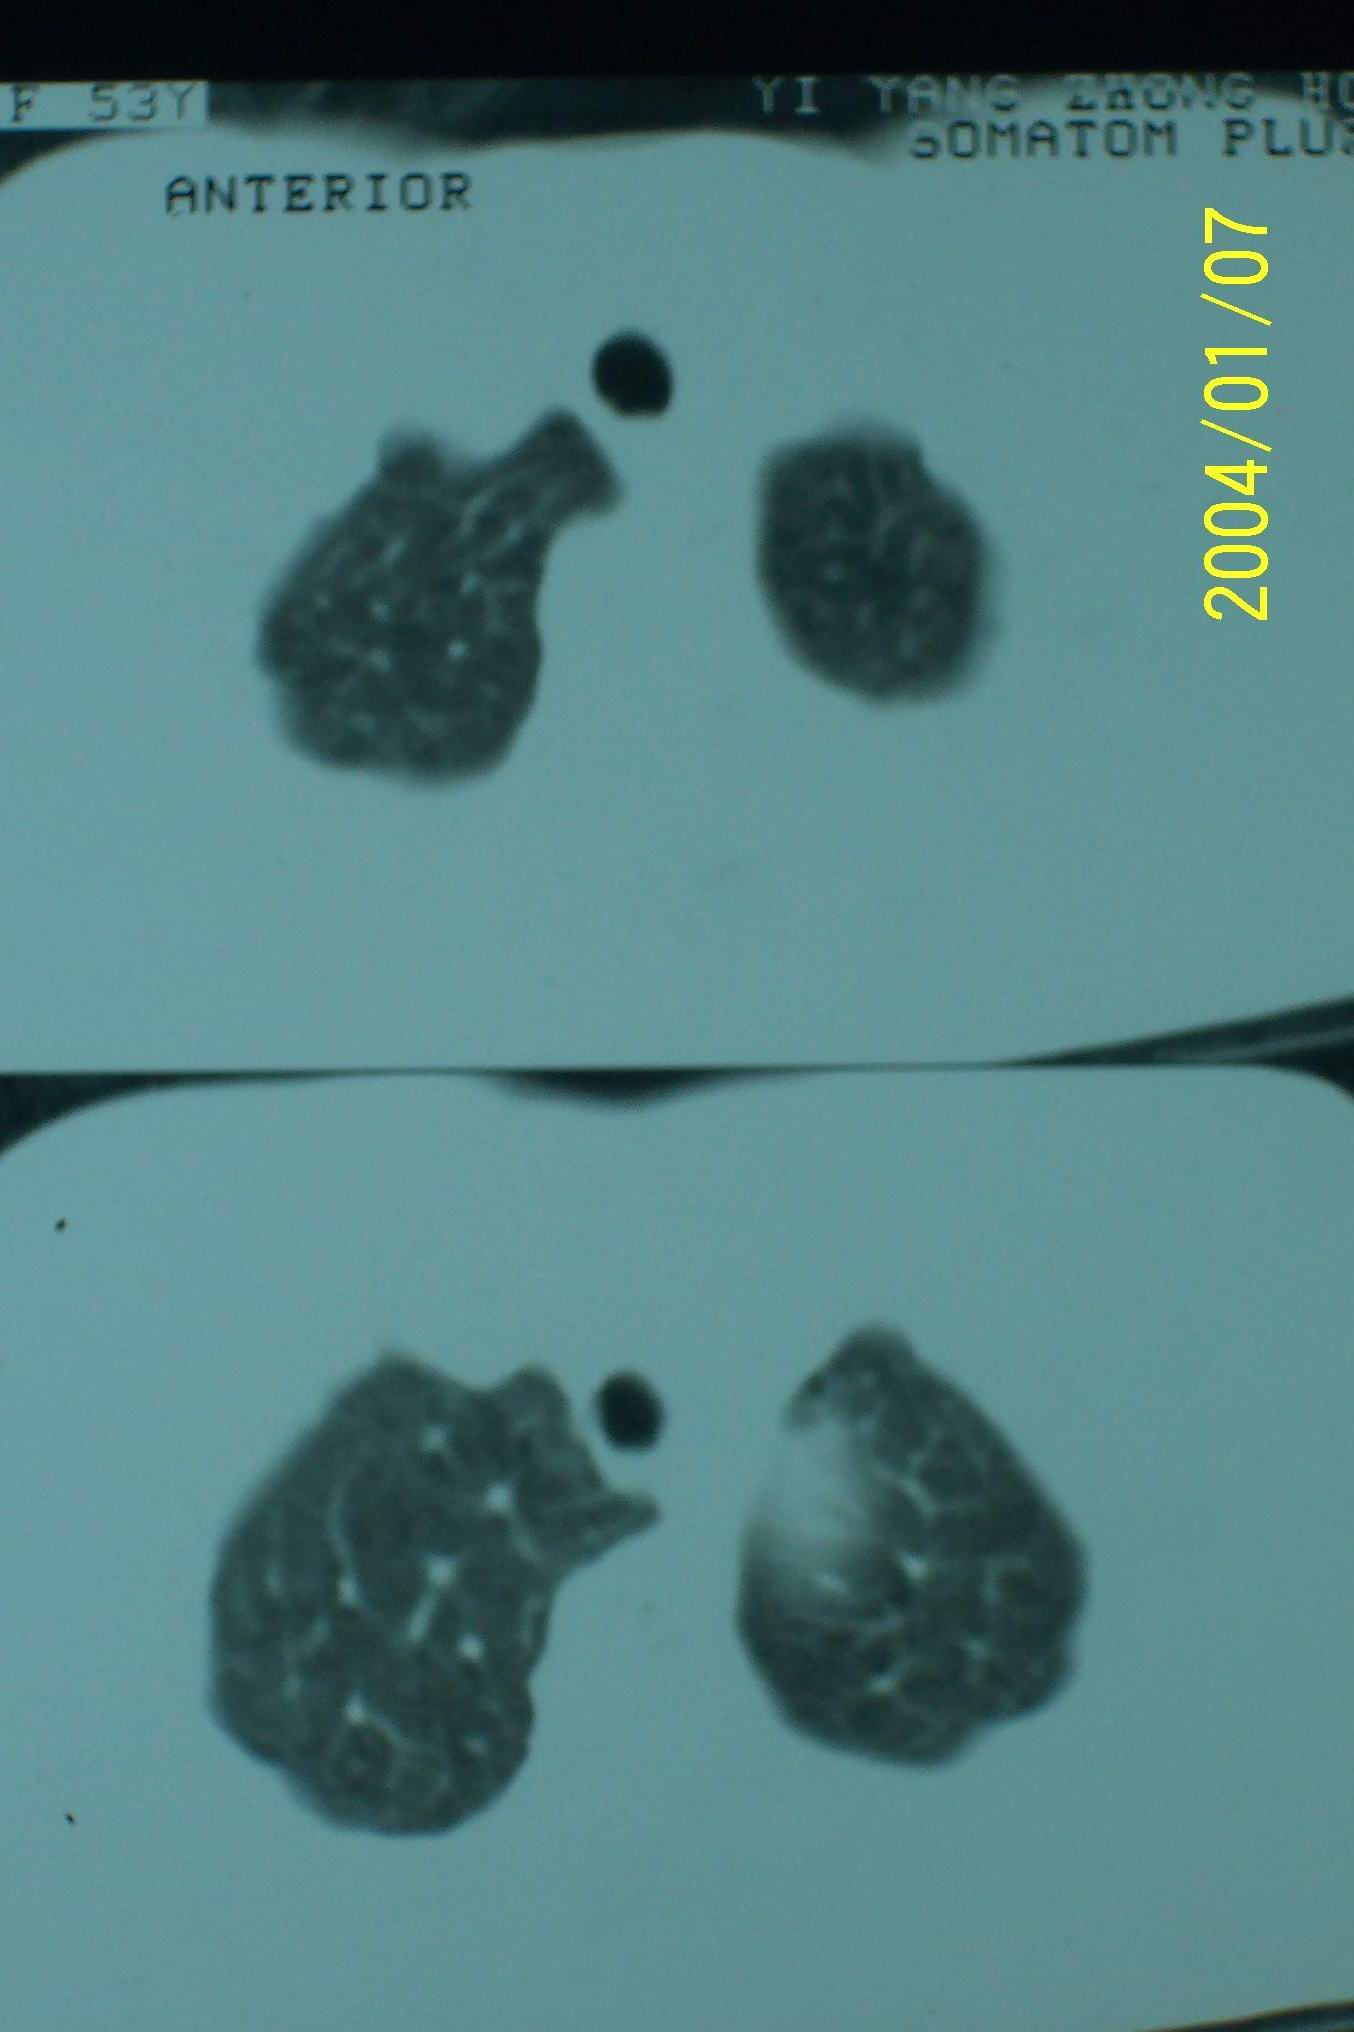

左肺下叶后基底段片状实变影,密度均匀,左肺体积缩小,膈肌上提.考虑:左下肺肺不张.

1.左侧胸腔无明显萎陷,肺体积缩小,含气量减少,纵隔心脏左移。从这个意义来讲,左下肺病灶应该首先考虑肺不张。

2.左下肺病灶密度太过均匀,边缘过于光整锐利,位置特殊,其次应该考虑隔离肺的可能。

3.连续观察不能完全否定病灶是疝入胸腔的脾脏(扫描不怎么规范,跨越过大),所以膈疝也需要考虑。

从连续观察的层面看象是疝入的脾脏